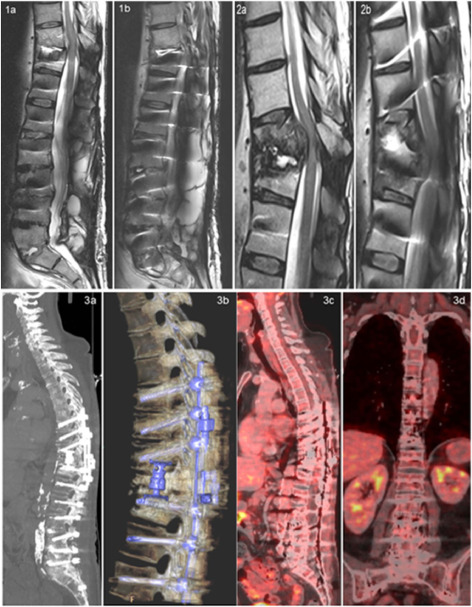

A woman aged 60, with vertebral osteomyelitis and discitis, having a non-removable implant, was diagnosed with chronic MRSA and received multiple antibiotic regimens. Over the course of time, the patient developed hypersensitivity to most available antibiotics. The case was further supported by FAGOFARMA, a biotechnology company specializing in bacteriophage-based research and therapeutics. The main focus of this Spanish company is on the development, research, and production of biotechnological preparations based on bacteriophages and transfer it into clinical practice.

Targeted bacteriophages were matched to the patient’s isolate and administered alongside antibiotics. The patient received around 35 intravenous doses of anti-staphylococcal bacteriophage therapy with antibiotics, which was administered with approval from the National regulatory authority, over a period of 8 weeks. As the bacteriophages are specific to the target bacteria, the patient responded well, with no adverse events observed, and now remains in good clinical condition without signs of infection relapse.